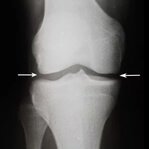

Osteoartrita distruge treptat țesutul cartilaginos și duce la deformarea articulațiilor. În timp, chiar și cele mai simple mișcări devin imposibile, iar durerea devine constantă. O terapie corectă ajută la încetinirea progresiei bolii.